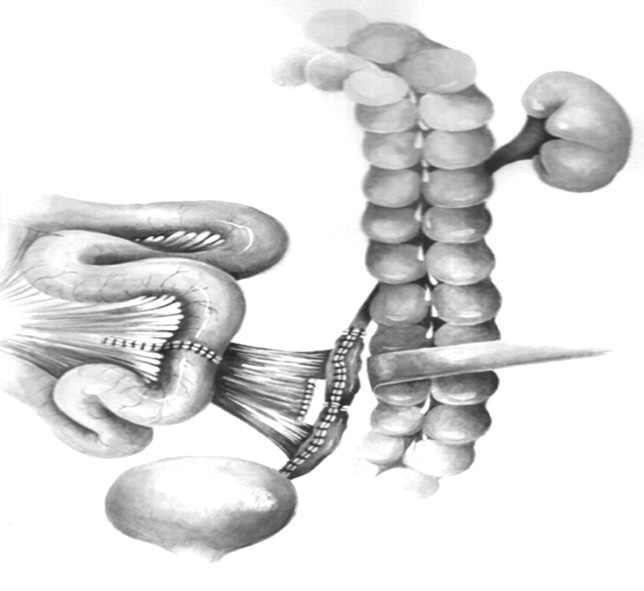

Bilateral small intestinal reconstruction of the ureters was performed in 40 (20.7%) patients. Most often, in 24 (60.0%) patients, U-shaped ileoureteroplasty was performed (Figs. 8 and 9), and more complex reconstructions were performed less often; that is, Y-shaped in 1 (2.5%) case, J-shaped in 3 (7.5%), L- and 7-shaped (Figs. 10 and 11) ileoureteroplasty in 6 (15.0%), and that with two separate ileografts in 6 (15.0%) cases.

Fig. 10. Bilateral isoperistaltic 7-shaped ileoureteroplasty

Fig. 11. Multisection computed tomography (MSCT) with contrasts of the patient 5 years after bilateral isoperistaltic 7-shaped ileoureteroplasty

Bilateral ileoureteroplasty is a more complex and traumatic surgical procedure. Most often, the need for the procedure arises in case of radiation damage to the urinary tract. Partial or complete replacement of both ureters can be performed simultaneously or in stages using one or two separate segments of the bowel. The staged approach to surgery depends on the severity of the patient’s condition and destructive changes in the urinary tract. Bilateral ileoureteroplasty becomes more complicated because the length of the ureteral sections requiring replacement increases. This is due to (1) a wide and traumatic surgical approach; (2) the need to exclude a more extended segment from the small intestine; (3) the inclusion of a long convoluted segment(s) of the intestine into the urinary system, which leads to a larger area of resorption and an increased risk of metabolic disorders; and (4) the abovementioned complicated aspects of plastic surgery of the right ureter in the isoperistaltic position.